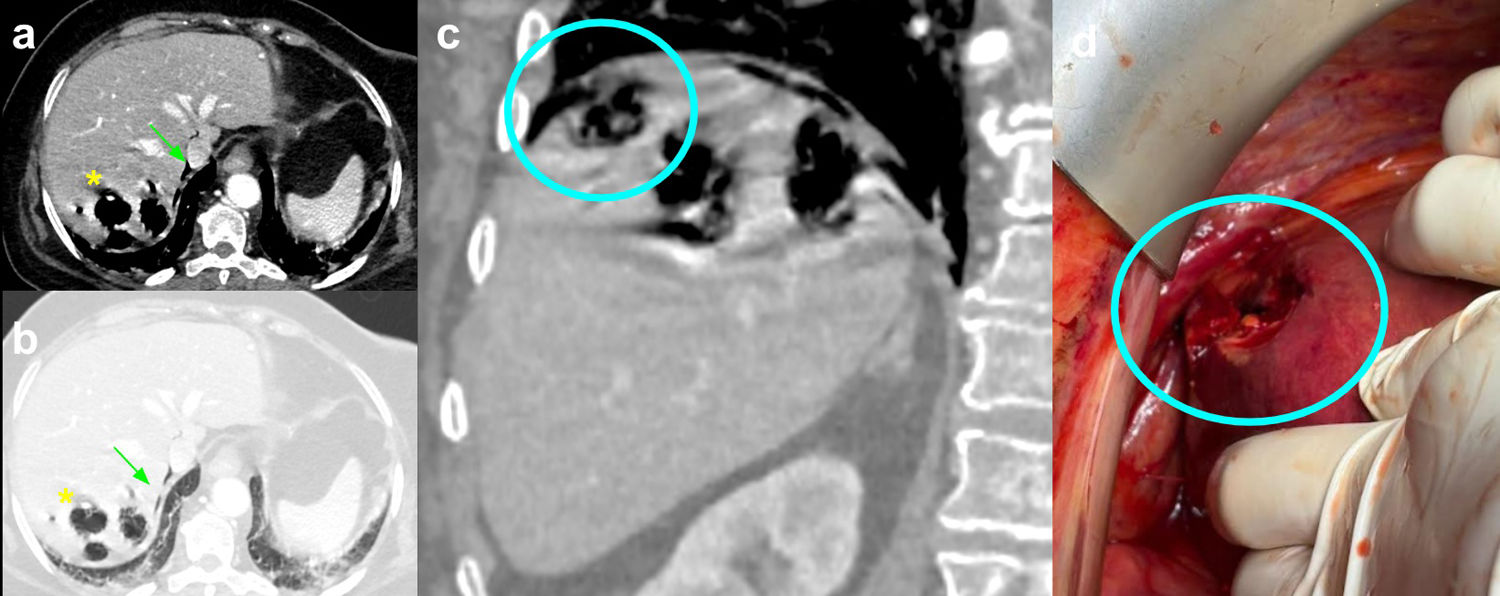

Hepatitis enfisematosa: diagnóstico radiológico y correlación intraoperatoria de una patología infecciosa extraordinariamente infrecuente

Emphysematous hepatitis: radiological diagnosis and intraoperative correlation of an extremely rare infectious disease